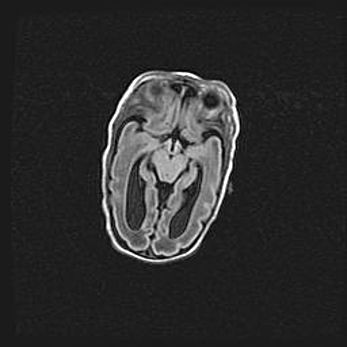

Сообщающаяся гидроцефалия. Кистозная энцефаломаляция головного мозга.

Возраст: 3 месяца 4 дня

Вес: 3100 г

Пол: женский

Окружность головы: 34 см

Срок гестации: 31 неделя

Кистозная энцефаломаляция головного мозга - одна из форм поражения головного мозга в детском возрасте. Характеризуется возникновением множественных и распространённых кист в коре, белом веществе и подкорковых образованиях головного мозга у плодов, новорождённых и детей раннего возраста. Развитие кистозной энцефаломаляции связано с внутриутробной асфиксией и гипотонией, родовой травмой, тромбозом синусов, пороками развития сосудов, инфекциями, сепсисом и другими причинами. Наиболее значимые инфекционные агенты: вирусы простого герпеса, цитомегалии, краснухи, токсоплазмы, энтеробактерии, золотистый стафилококк и другие.